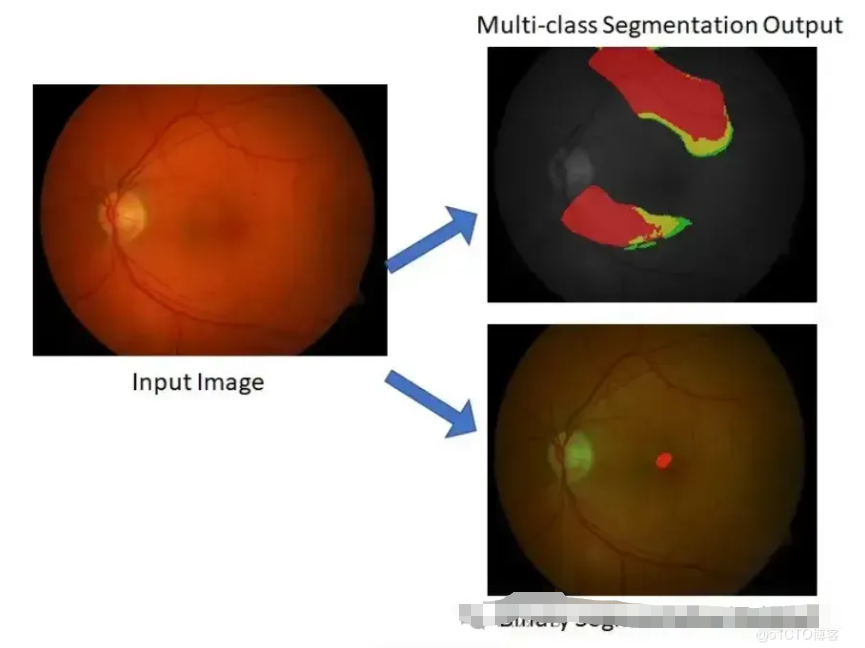

【1】您能解释一下什么是UNet架构以及它是如何使用的吗?

UNet 架构通常在大型带注释图像数据集上进行端到端训练,以预测每个图像的像素级分割图。可以训练模型来分割单个类别或多个类别,具体取决于具体任务。

UNet 广泛应用于各种图像分割任务,例如医学图像分割、卫星图像分析和自动驾驶车辆中的目标检测。它以其处理高分辨率图像和生成准确分割图的能力而闻名。